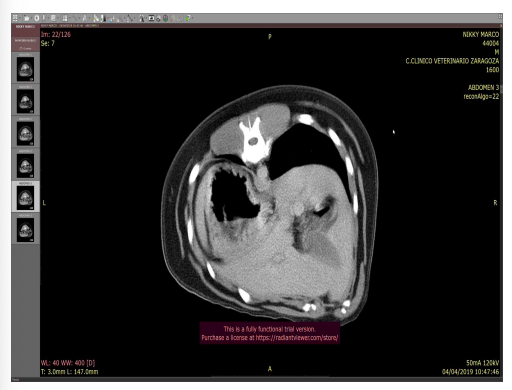

Para confirmar el shunt porto sistémico ( Anastomosis porta-cava caudal ) hace falta ecografia principalmente aunque escintigrafia tambien ayuda. Con Tac (TC) + contraste

Un shunt circulatorio es una conexión anormal o un desvío del flujo normal de un líquido, como la sangre, entre dos partes del sistema circulatorio o hacia otro sistema

- Sospechas de malformaciones arteriovenosas y SPS

- Contraste en vaso periférico

- Excelente representación anatómica del origen, determinación y curso del vaso anómalo

- Reconstrucción 3D

- Plan prequirúrgico (masas)